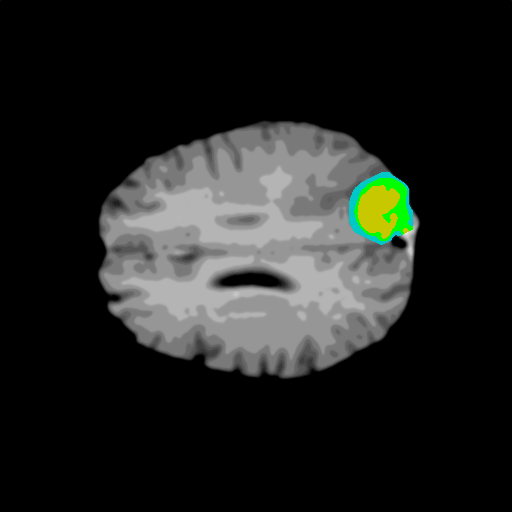

Extensive experiments have been performed in the current setup, and experimental outcomes are reported with the demonstration of numerical and statistical analyses using the proposed QFS-Net, QIS-Net [39], convolutional U-Net [18] and Residual U-Net (URes-Net) architectures [20]. The human expert segmented skull-tripped contrast enhanced DSC brain MR input image slices of size and ROIs are provided in Figure 5 as samples. The demonstration of QFS-Net segmented images followed by the essential post-processed outcome on the slice no. for class level with four distinct activation schemes () are shown in Figure 6. It is evident from the experimental data provided in Table LABEL:tab1 that the proposed QFS-Net performs optimally for the -connected quantum fuzzy pixel information heterogeneity assisted activation () with and gray scale set in comparison with other thresholding schemes and gray scale sets under the four evaluation parameters () [44]. The segmented tumors obtained using the proposed self-supervised procedure under class transition levels with four different thresholding schemes , , and are demonstrated in Figures 7- 8 for the class boundary sets and [39], respectively. The segmented images using the remaining two class boundary sets ( and ) [39] are provided in the supplementary materials section. The segmented ROIs describing the whole tumor region after the masking procedure using QIS-Net, U-Net and URes-Net are also reported in Figure 9.